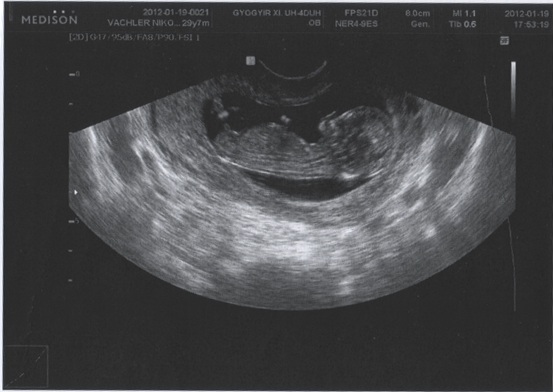

Nemrég értem haza az UH-ról :) Már egy óriásbébi mocorgott a képernyőn, nagyon cuki volt. 50 mm az ülőmagassága és minden okés vele, a nyaki redő értékünk is teljesen megfelelő.

És íme egy kép a mi kis gyönyörű babácskánkról:

Kép Kistesó

A neméről annyit, hogy bár biztosra nem mondta, de úgy látta, hogy mintha lenne a lába között valami fütyi féle... mindenesetre a reményt még nem adom fel, hogy egy gyönyörű kis hercegnőnk születik...